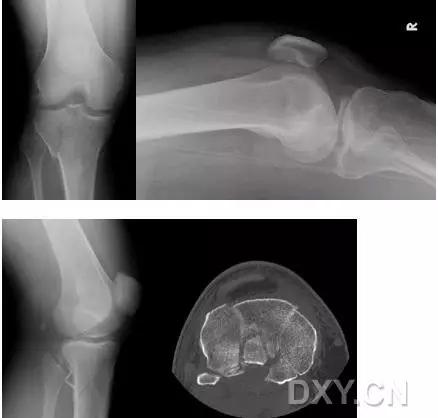

11. Bumper 骨折 (保险杆骨折)

是汽车保险杠撞击膝关节外侧,导致的胫骨平台粉碎性骨折,伴有软骨面挫裂和腓骨头骨折。初诊,X 线上正侧位很容易忽略平台的粉碎性,CT 平扫及重建可明确伤情,MRI 可了解副韧带及叉韧带情况。